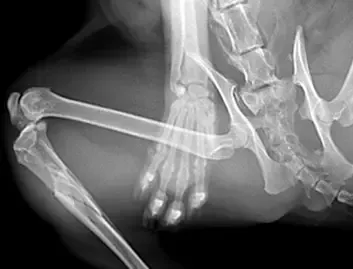

Polytrauma and Complex Trauma Surgeries

Expert trauma surgeons deliver life-saving care, managing multiple and complex injuries with advanced techniques, ensuring stability, recovery, and improved quality of life.